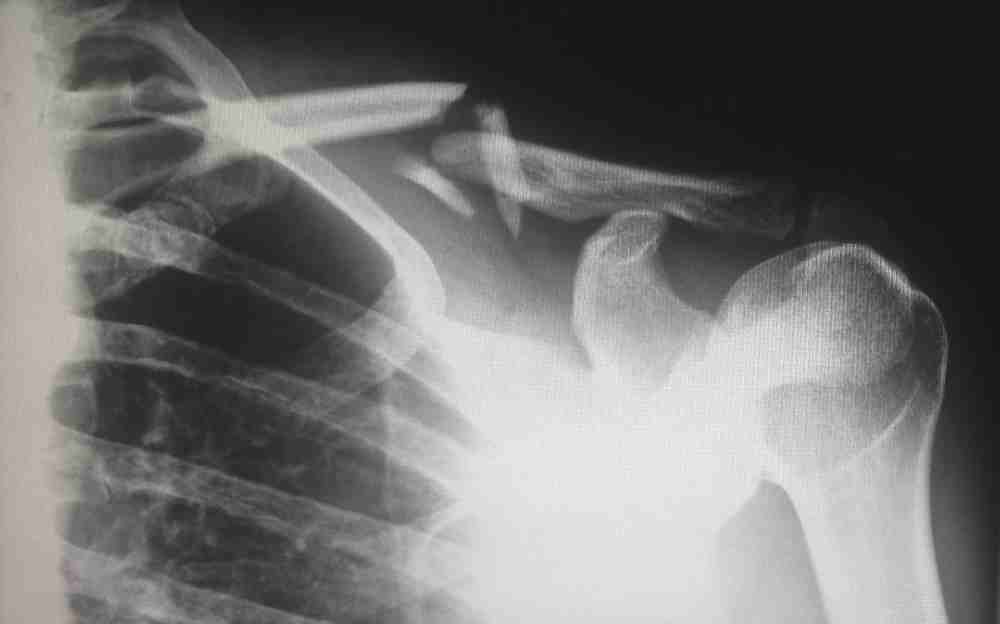

Workplace injuries can range from minor cuts or bruises to serious, life-threatening conditions. They can occur in any type of work setting, but are more prevalent in labor-intensive jobs, involving heavy machinery, manual handling of materials, or repetitive tasks. Regardless of the injury’s severity, it’s vital to understand the underlying legal and medical implications.

Common workplace injuries typically include falls, repetitive motion injuries, manual materials handling injuries, slips and falls, and motor vehicle accidents. In some cases, exposure to toxic substances or hazardous environments could lead to long-term health complications. You can learn more here about workplace injuries and what you can do to get your compensation, Recognizing the types of injuries prevalent in your workplace can help in implementing effective prevention strategies.